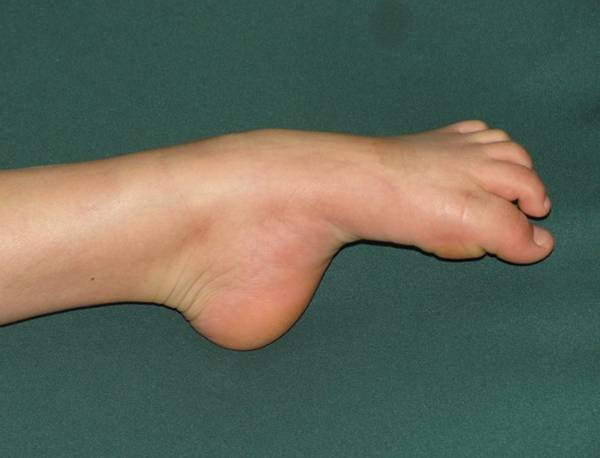

共同讨论一个病例:

半年前患儿洗脚时无意中发现右足踇趾不能伸直,后此症状无变化。

查体:右踇趾下垂,屈曲位不能伸直,被动伸直可,右踇趾感觉正常。右足2-4趾背伸力量减弱,右足2-4趾短伸肌肌腹处未触及肌肉主动收缩。左足伸踇趾及其他足趾伸趾力量减弱。

左踇趾肌力0级

2-5趾4级

右踇趾肌力3级

2-5趾5级弱

小儿神经科会诊,未明确诊断